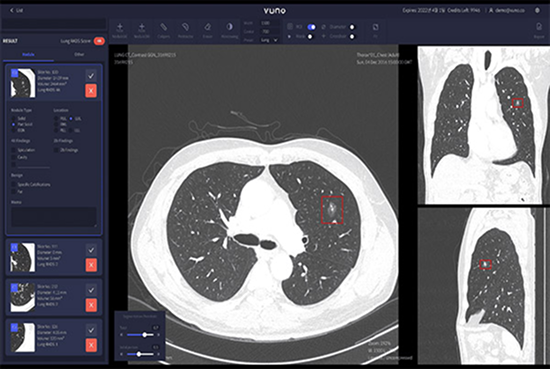

VUNO Med-LungCT’s competitive edge is about its performance. An AI-based product that assists lung diseases diagnosis, it also provides data on nodules’ size, volume, and location.

Results are integrated with PACS in the format of GSPS objects, which ensures great user convenience.

• High Sensitivity, 93% Sensitivity per 1 FP, based on performance validation with open dataset LUNA16

• Optimized nodule detection performance through super-resolution algorithm

• Detects nodules between 4mm — 30mm

• Provides volumetric data of nodules

• Provides a mask feature to detect part-solid nodules (Overall, Ground-glass, Solid Part)